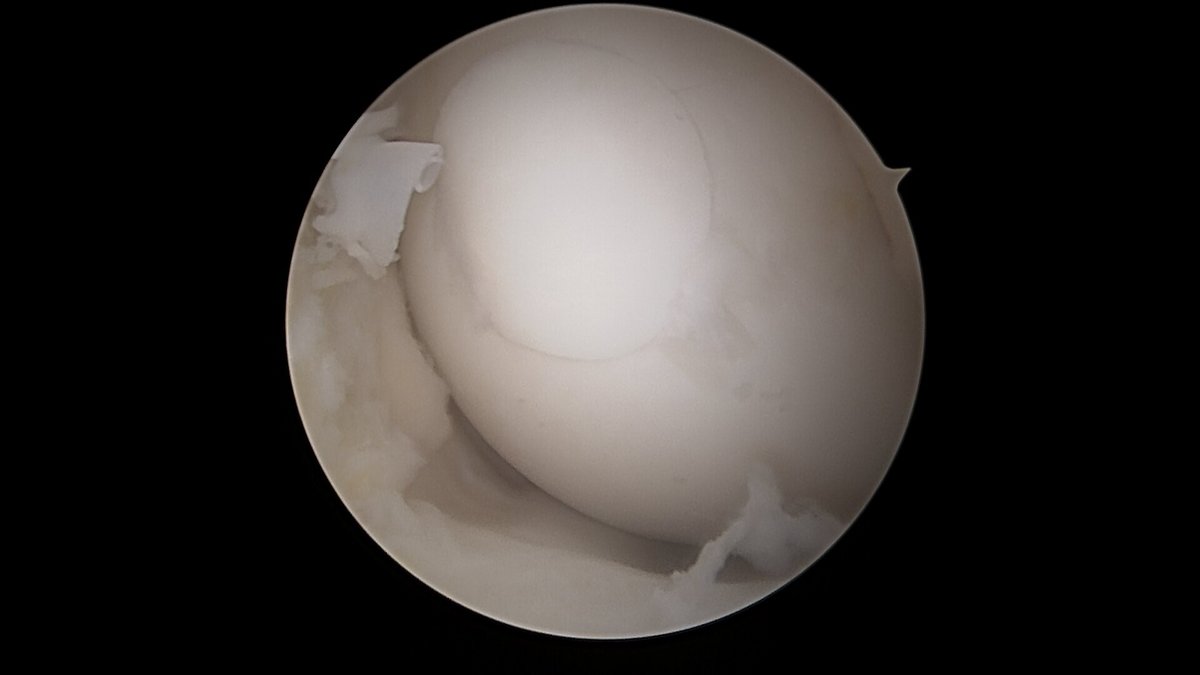

Eine der häufigsten Sportverletzungen im Bereich des Kniegelenkes ist die vordere Kreuzband-Ruptur. Vor allem bei jungen, sportlich aktivem Patienten ist oftmals eine sogenannte VKB-Ersatzplastik notwendig. Goldstandard ist der Ersatz des gerissenen Kreuzbandes durch eine körpereigene Sehne, ggf. können noch stehende Restfasern als Leitstruktur belassen werden. Hierzu stehen verschiedene Transplantate zur Verfügung (Hamstring-Sehnen, Quadrizepssehne, …) die individuell ausgewählt werden. Zusatzverletzungen des Meniskus oder der Seitenbänder werden ebenfalls im Rahmen der Operation behandelt. Das Kreuzband wird über Bohrkanäle an die anatomische Position gebracht und dort mittels sog. Interferrenzschrauben im Kanal verblockt.